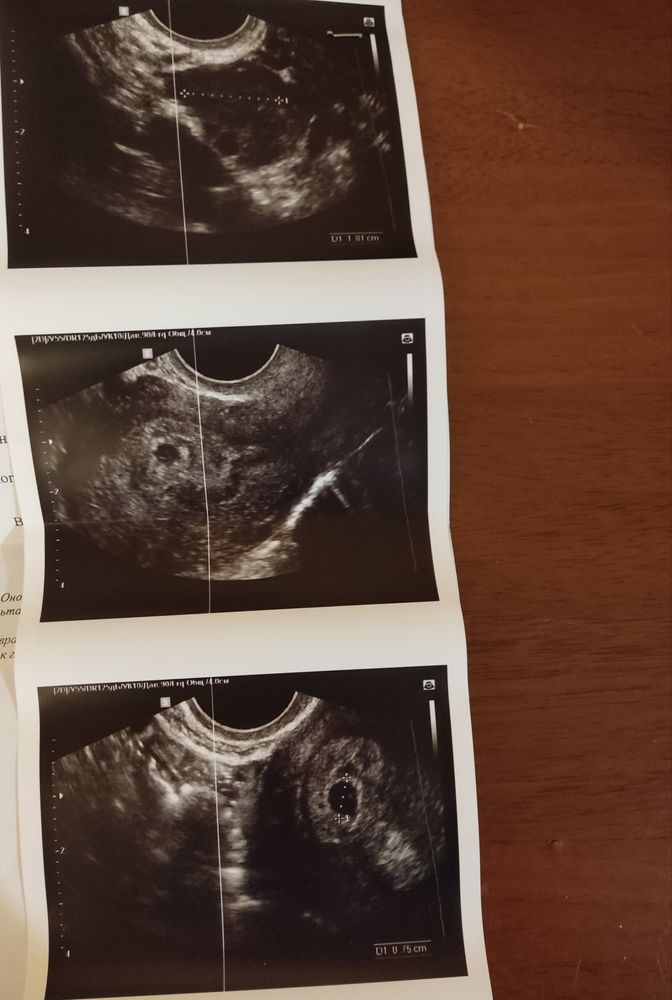

Девочки, привет, сходила на УЗИ сегодня, наконец то всë увидели. Больше всего боялась внематочной беременности, и слава богу, меня это обошло. Теперь можно ближайшее время быть спокойной)